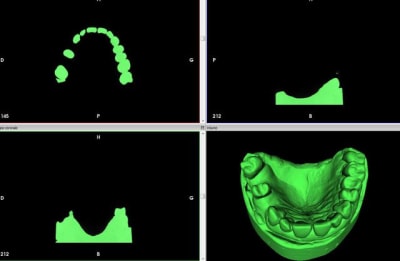

1) plâtre cône beam dans invesalius

2) cone beam vs cam3d

3) collage dans blender

4) résultat